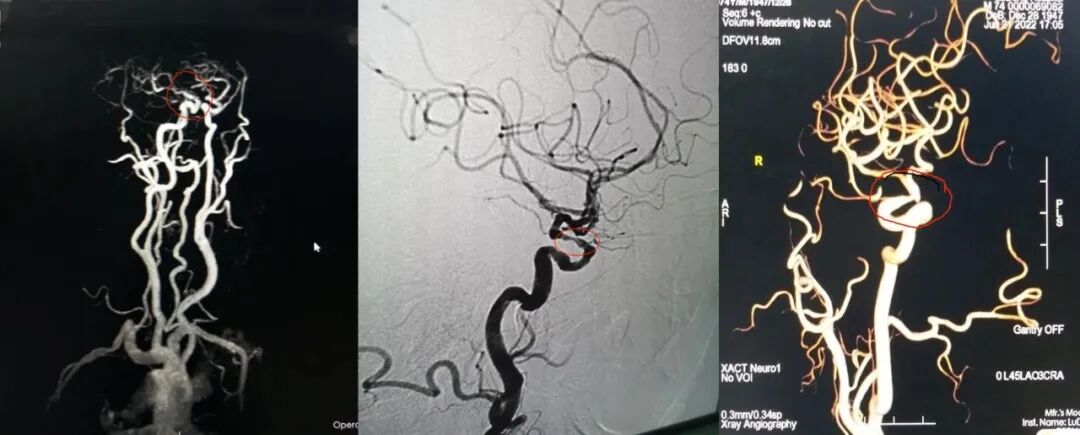

导丝怎么扩【载药时代 球扩天下】NOVA DES®颅内药物洗脱支架在症状性颅内动脉狭窄中的应用—烟台鲁东医院使用体会二例!_https://www.jmylbn.com_新闻资讯_第6张

LVA狭窄90%

重要影像结论:左椎动脉V4重度狭窄,大于90%,右椎动脉纤细远端闭塞。

微导丝置于大脑后动脉远端,造影显示左侧V4段重度狭窄,前向血流显著延迟。